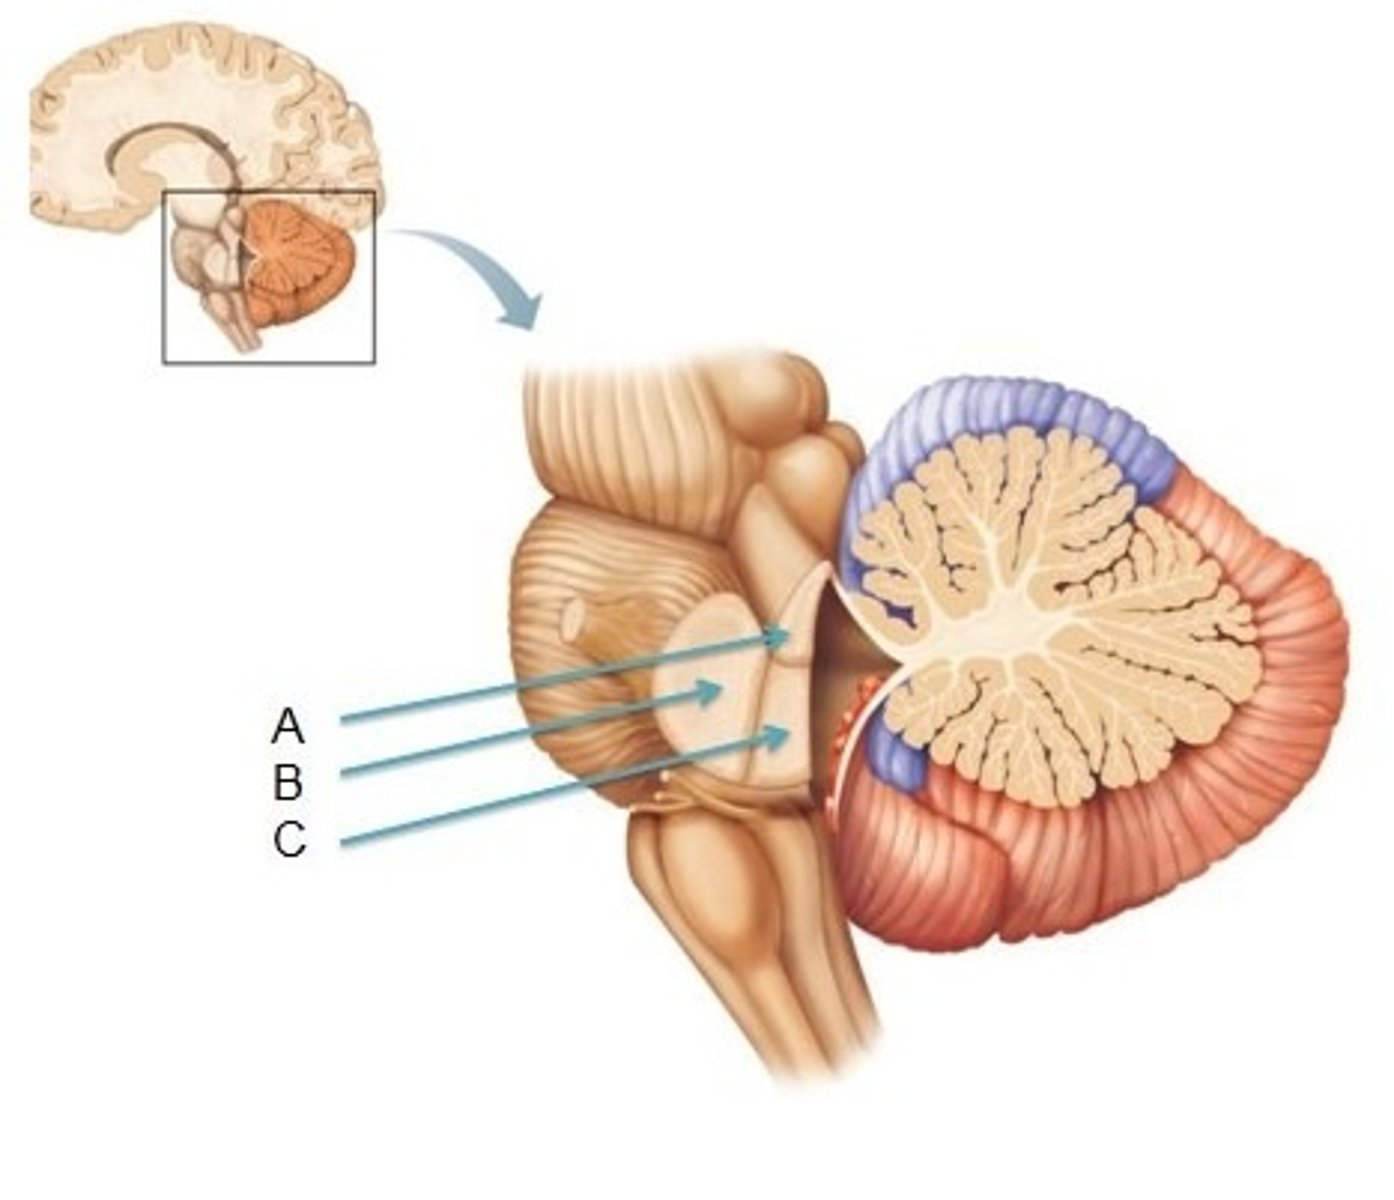

What is the superior boundary of the pons?

isthmus of the brain stem (between pons and cerebral peduncles)

What is the inferior boundary of the pons?

pontomedullary junction

refers to the large round protuberance on the ventral pons that represents a "bridge" of horizontally oriented fibers connecting the right and left sides

basilar portion

longitudinal midline groove of the pons that is the superior continuation of the ventral median sulcus/fissure, containing a namesake artery

basilar sulcus

white matter stalks that connect the pons to the cerebellum

middle cerebellar peduncles

What is the only cranial nerve that attaches to the pons?

CN V

portion of the pons that is dorsal to the basilar portion and represents mostly longitudinally oriented fibers and cranial nerve nuclei

**also helps to form the floor of the 4th ventricle

tegmentum

A

basilar portion

B

basilar sulcus

C

CN V

B

middle cerebellar peduncles

tegmentum